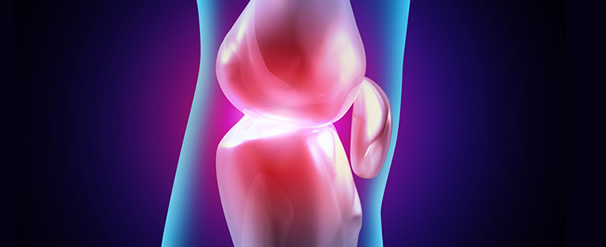

¿Cuanto tiempo duran estas prótesis?

Las prótesis metal-metal se vienen implantando desde hace 10 años, por lo que no está demostrada su duración. Esto ocurre con cualquier avance o novedad, pero lo que sí sabemos es que las prótesis con polietileno tienen una duración limitada a 15 A 20 años. Se cree que las resurfacing metal-metal no tienen esta "caducidad" por su menor desgaste y pueden durar 25-30 años ( no se sabe) y con esta expectativa se están colocando de forma creciente en todo el mundo llegando a 90.000 implantes en la actualidad (en un solo Hospital británico se han colocado 4.000).

¿Por qué mi médico me aconseja esperar?

Es comprensible la actitud de un buen número de cirujanos que prefieren lo seguro y probado a lo novedoso. Pero esta posición va cambiando conforme se evidencia que éstas nuevas prótesis son aprobadas por exigentes agencias de control sanitario como la FDA en EEUU; asimismo la mayoría de grandes marcas de prótesis tienen su modelo y va creciendo el porcentaje de cirujanos entrenados en el nuevo procedimiento (más dificil tecnicamente). La bibliografía en revistas especializadas crece exponencialmente mostrando excelentes resultados.